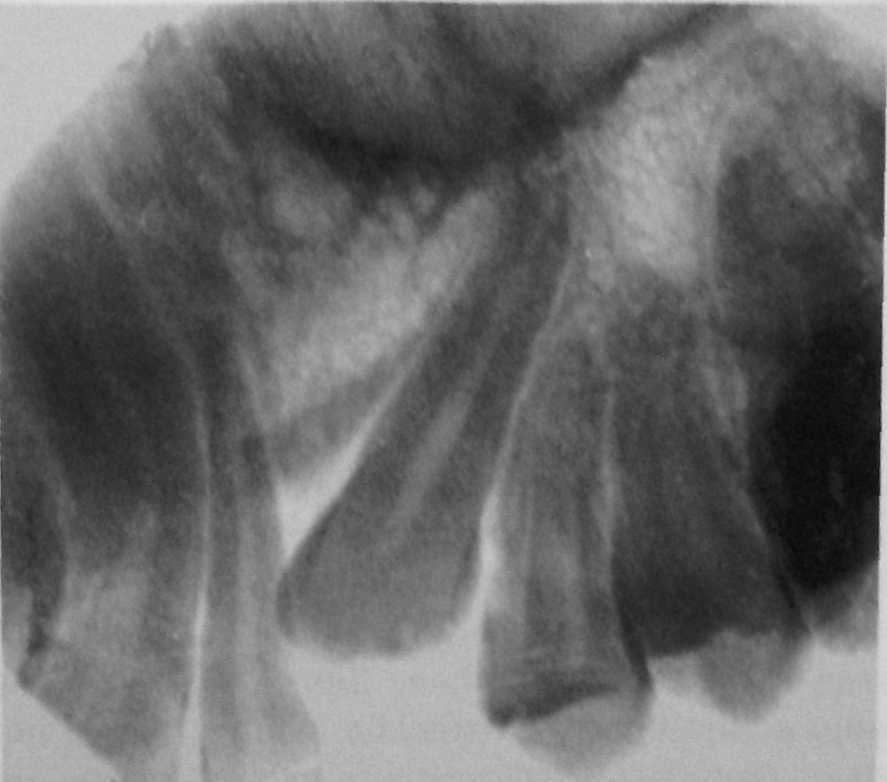

Рентгенография небного шва: Медицинские исследования и диагностика